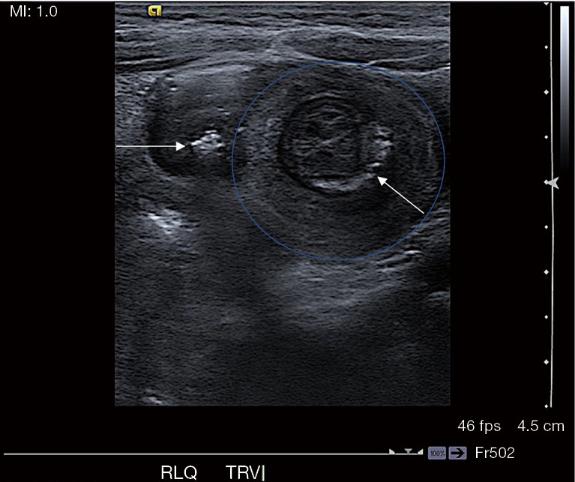

初步检查包括全血细胞计数、腹部X线和腹部超声(US)及平片(图1)。初始白细胞计数为19.6×109/L 腹部超声显示回结肠肠套叠,肠套叠部位有致密碎屑(与沙子一致)(图2)。腹部X光显示右下象限气体缺乏,与回结肠肠套叠的推测诊断相符。患儿被转诊以进一步治疗。

图2、超声显示右下象限肠套叠,目标征为肠壁的交替高回声和低回声环(蓝圈)。肠套叠内也可见回声砂粒聚集(白色箭头)